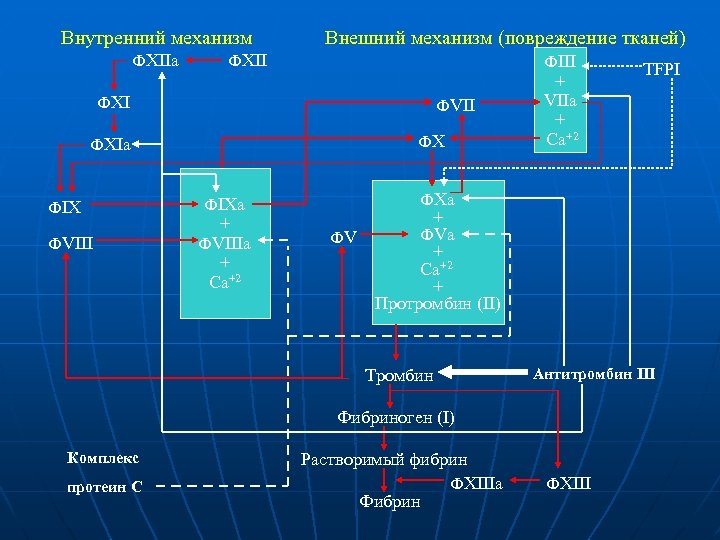

Внутренний механизм ФXIIa Внешний механизм (повреждение тканей) ФXII ФIII ФXI ФVII ФX ФXIa ФIX ФVIII ФV + ФVa + Ca+2 + Протромбин (II) Тромбин Антитромбин III Фибриноген (I) Комплекс протеин С TFPI ФXa ФIXa + ФVIIIa + Ca+2 + VIIа + Са+2 Растворимый фибрин ФXIIIa Фибрин ФXIII